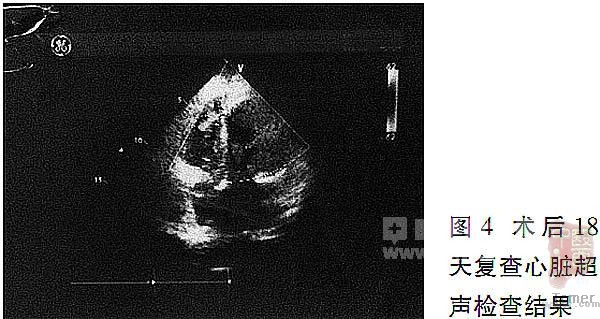

术后18天复查心脏超声(图4),结果显示,左心室较术前略有减小,前后径为5.2 cm,室间隔靠近心尖部探及补片强回声,极少量分流,射血分数(EF)有所提高,达52%。